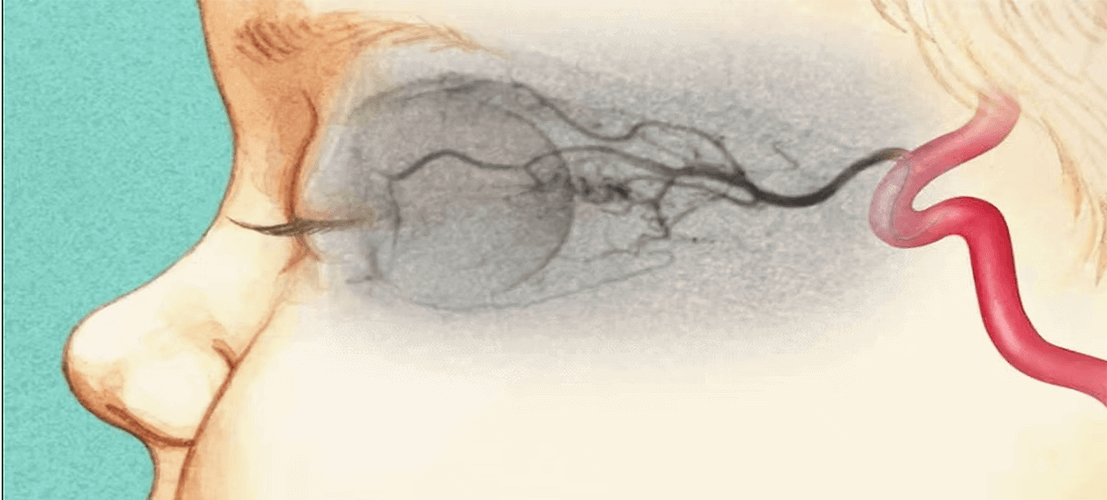

In order to treat tumors more effectively, the idea of administering the chemotherapy drug through the feeding arteries was first applied in head and neck tumors in the 1960s. Then, intraarterial chemotherapy has been widely used in many organs and regions. One of the tumors where intraarterial chemotherapy was  most successful is retinoblastoma, which is a common childhood eye cancer. Once, the only treatment for these patients was surgical removal of the eye, whereas today, in more than 95% of the patients, the disease can be cured by infusing chemotherapy to the eye artery (ophthalmic artery) and the eyes can be preserved. Intraarterial chemotherapy is theoretically applicable to tumors in each region or organ that can be reached by angiography in the body. However, in some tumors, some factors, such as the feeding vessels being too thin and too numerous, can make the process difficult. In general, intraarterial chemotherapy is most commonly used in liver, tumors, head and neck tumors and limb (limb) tumors. However, it is also used successfully for lung, breast and rectum cancers in some centers and hospitals in the world.

Intraarterial chemotherapy is a procedure similar to cardiac angiography for the patient. After entering  the groin artery under local anesthesia, the arteries of the organ where the tumors are located are catheterized using special catheter and guide wires. Serial angiography runs are then taken to identify the arteries that feed and do not feed the tumor. Subsequently, a much thinner and softer catheter (microcatheter) is advanced through the main catheter and placed into the feeding vessel closest to the tumor, but covering all the vessels going to the tumor. After this stage, the chemotherapy drug is infused directly into the tumor for 1-2 hours through the microcatheter. Since intraarterial chemotherapy is an angiographic procedure, compression must applied to the groin after the treatment to prevent bleeding from the entry point, or special “closure devices” must be used to seal it. In any case, the patient stays in bed for up to 6 hours. After treatment, most patients can go home, but in some cases, 1-2 days hospitalization may be required.